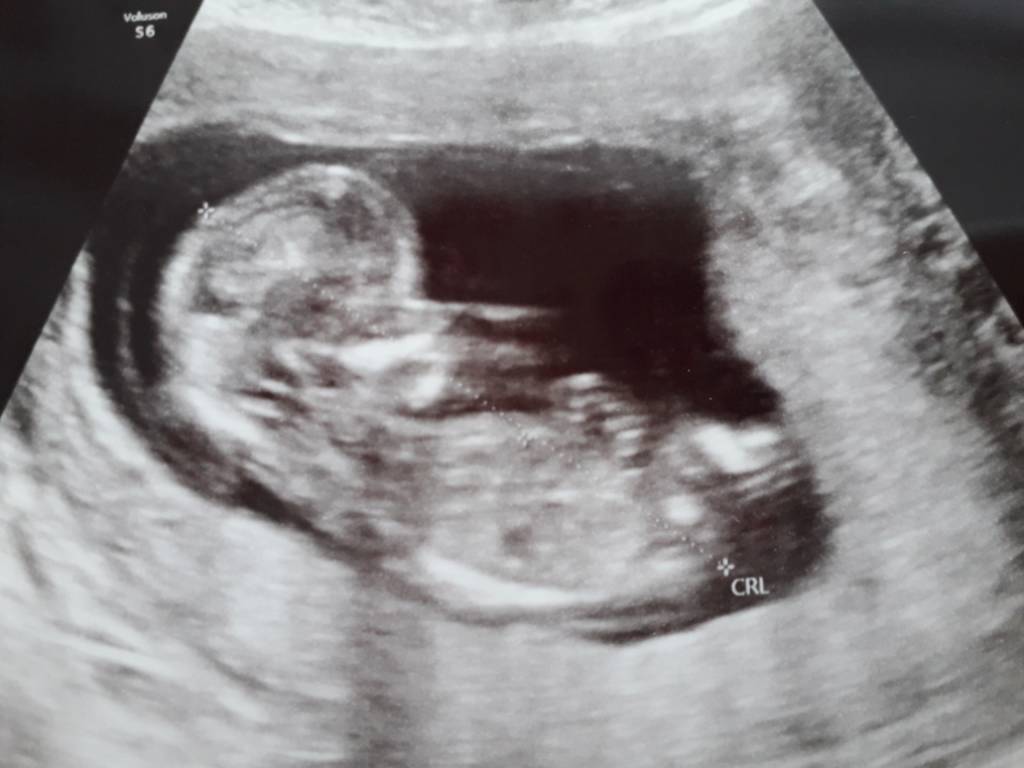

Ja już po wizycie. Wszystko ok!!!! Dr wszystko zbadala i wszystko w normie. Serduszko bije. Przeziernosc ok. A maluszek rusza się jak szalony. Adhd murowane [emoji23][emoji23] poki co nie wiadomo czy chlopiec czy dziewczynka.

Wrzucam zdjęcie mojego ludka [emoji7][emoji7] Zobacz załącznik 936883